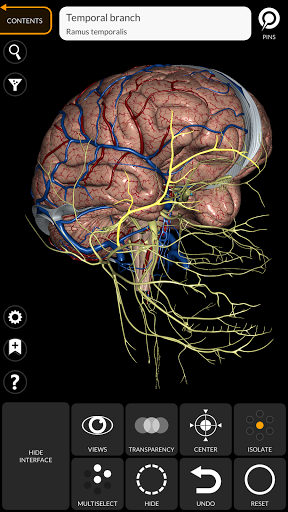

يتيح لك "Anatomy 3D Atlas" دراسة التشريح البشري بطريقة سهلة وتفاعلية.

من خلال واجهة بسيطة وبديهية، من الممكن ملاحظة كل بنية تشريحية من أي زاوية.

تتميز النماذج التشريحية ثلاثية الأبعاد بتفاصيل خاصة ودقة تصل إلى 4K.

• الجهاز العصبي

• من خلال تحديد نموذج أو دبوس، يظهر المصطلح التشريحي ذي الصلة